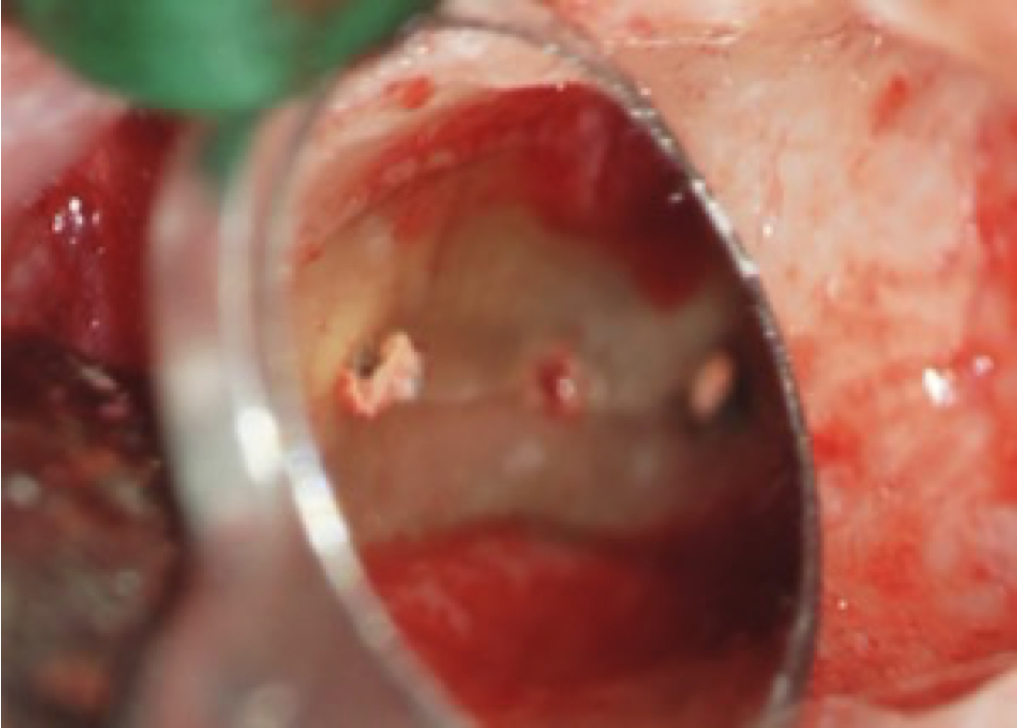

• WSR mit retrograder WF mit MTA Zahn 46

Nach orthograder Revision des resizierten Zahnes 46 persistierte der Entzündungsherd an der mesialen Wurzel eines 40 jährigen Patienten. Im leicht geschwollenen Vestibulum regio 46 imponierte ein Fistelmaul. Das Ausgangsröntgenbild zeigte eine ausgeprägte periapikale Osteolyse an der mesialen Wurzel von Zahn 46. Da der Zahn von orthograd austherapiert war, haben wir uns als Ultima Ratio zur Nachresektion der mesialen Wurzel entschieden. Dabei sollte das von der ersten Resektion verbliebene „Zahnscherbchen“ entfernt und die Wurzelkanäle von retrograd mit MTA verfüllt werden.

Nach Bogenschnitt und Mukoperiostlappen wurde das Granulationsgewebe entfernt und die Wurzelspitze nachresiziert. Mit Ultraschallansätzen konnten die 3 mesialen Wurzelkanäle auf eine Länge von ca. 4 mm retrograd aufbereitet und nach Blutstillung mit MTA verfüllt werden.

Schon nach 6 Monaten konnte man eine weit fortgeschrittene Reossifikation im Kontrollröntgenbild ausmachen.